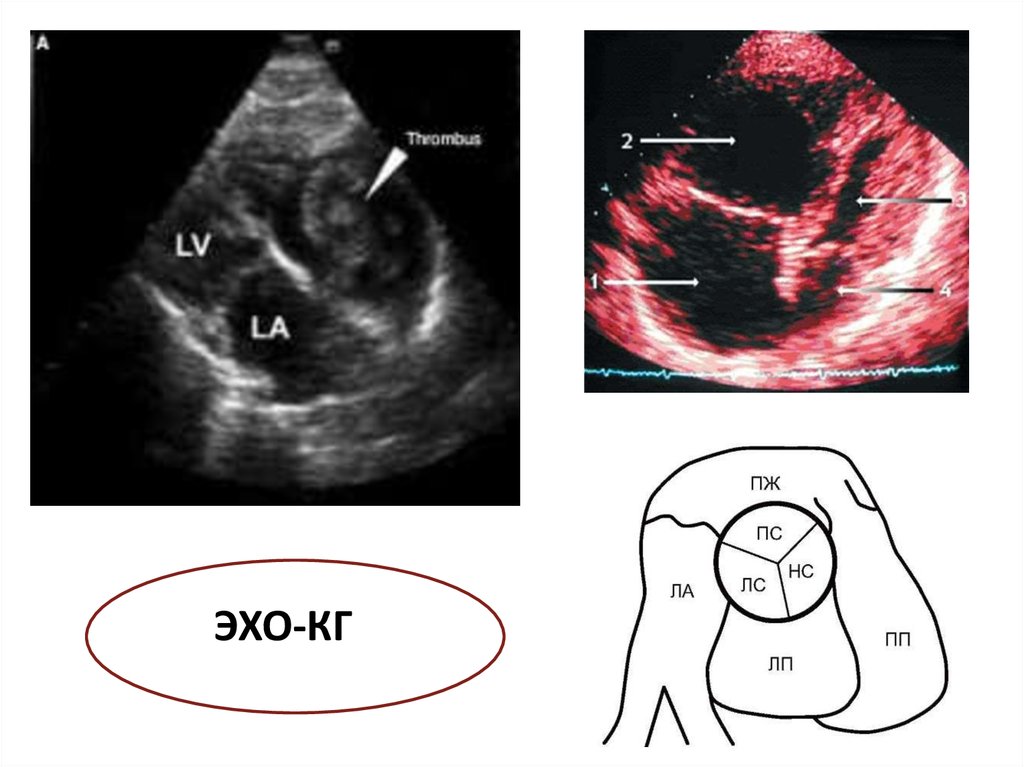

ЭХО-КГ

Дилатация ПЖ, гипокинез или

перегрузка давлением на ЭхоКГ